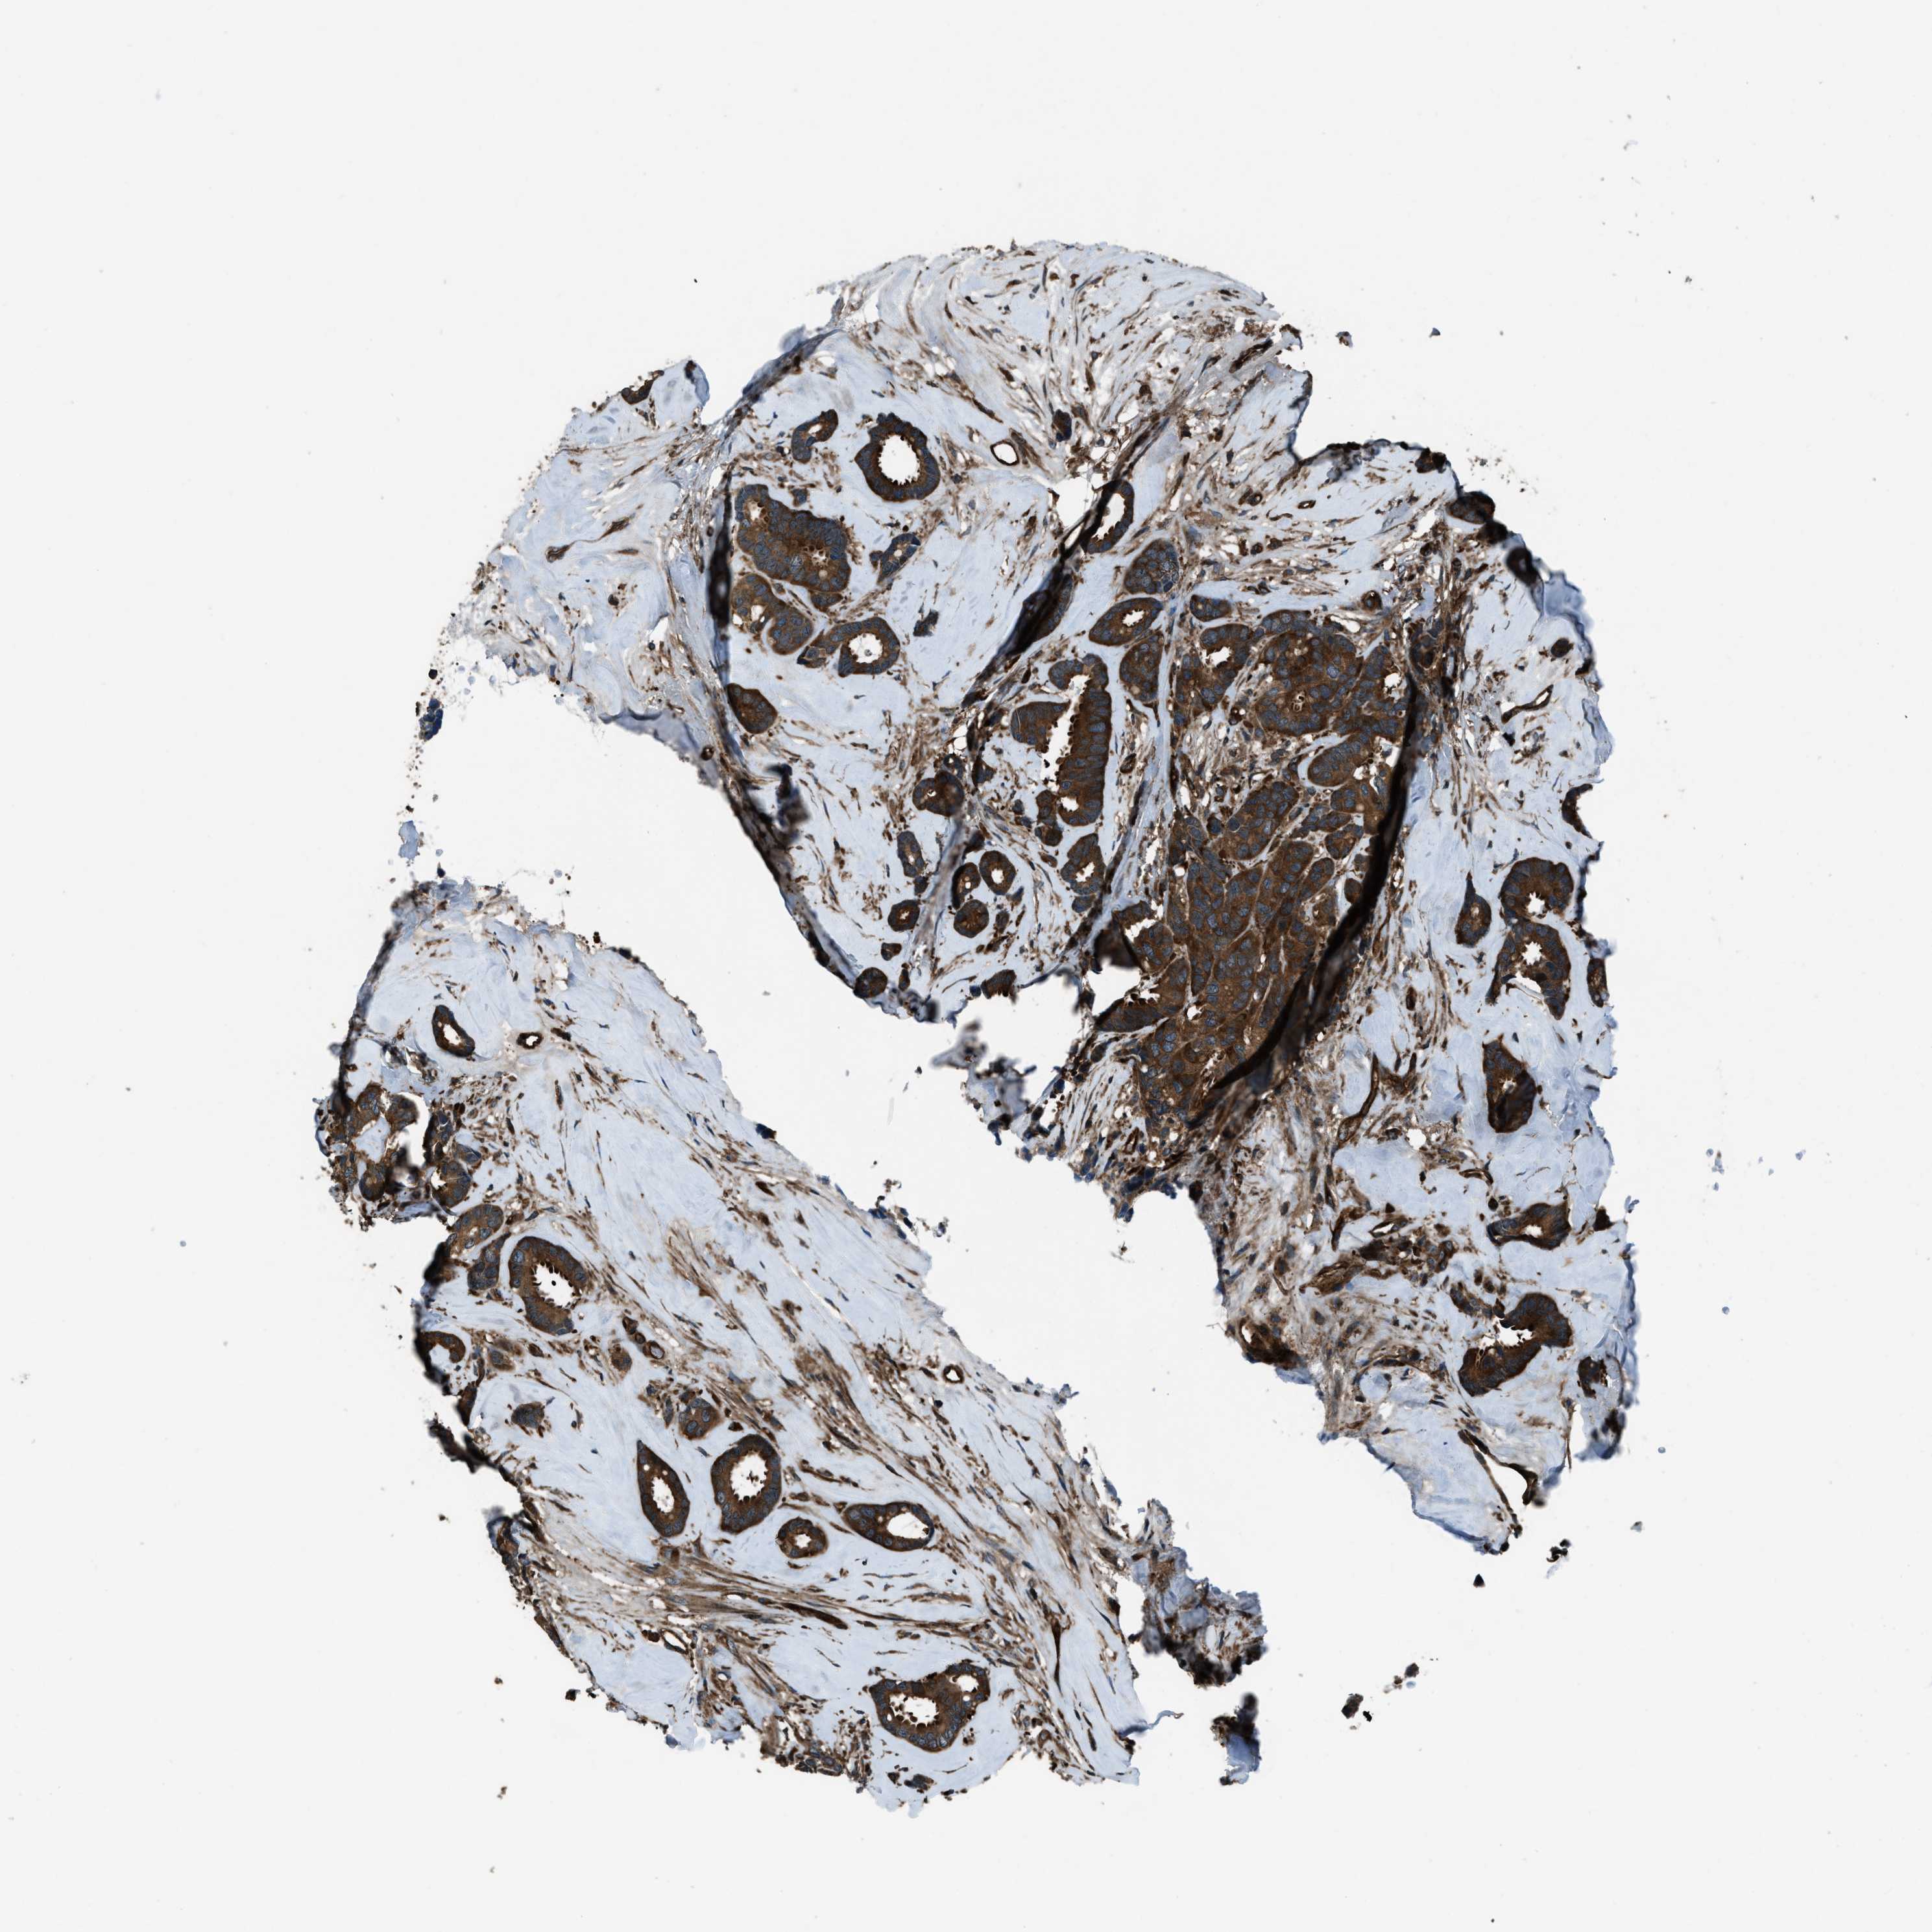

CANCER BREAST CANCER Show tissue menu

BRCA TCGA BRCA VALIDATION PROTEIN EXPRESSION